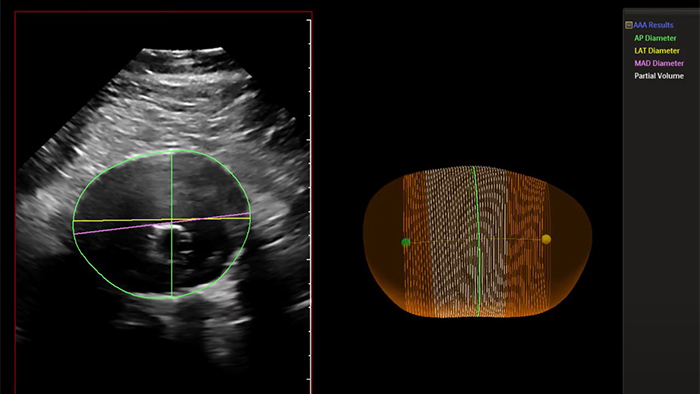

Philips AAA Model is a software application that helps clinicians detect, segment and quantify 3D ultrasound data for use in surveillance of native and post-endovascular aneurysm repair (EVAR) AAAs.